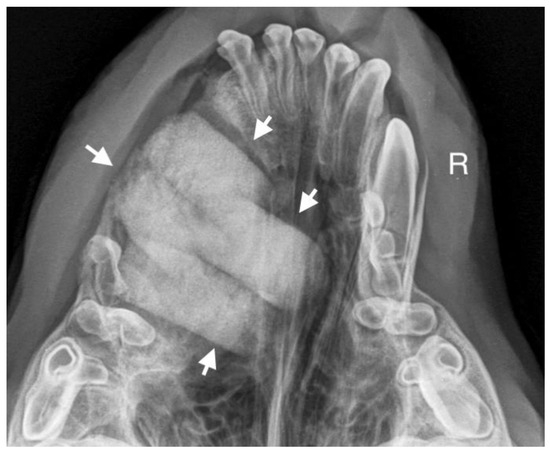

A 7-month-old male Rottweiler was referred for consultation because of severe swelling on the left side of the jaw, with a suspected jaw tumor. Clinical examination revealed no abnormalities in the aforementioned lymph glands and no soreness on palpation. Intraoral examination on the left side revealed severe asymmetry, with enlargement of the facial soft and hard tissues, an absence of permanent teeth, and buccal displacement of deciduous teeth. On the left side, rhinoscopic examination revealed normal anterior nostrils and a left nasal aperture with a lack of patency from the level of the nasal bony inlet to the posterior nostrils. A roentgenogram in the dorsal–ventral projection showed the presence of four ectopic teeth in the maxilla, with the formation of a dentigerous cyst (Figure 2). Using the CLP technique, the ectopic teeth were removed and the cyst walls were lanced. The bone loss caused by the cyst was 7.3 cm × 4.6 cm, and the jawbone left behind was too thin to provide a scaffold for the surrounding tissues and to ensure nasal cavity patency. From a 5 cm pellet of hydroxyapatite polymer material with curdlan previously soaked in saline (according to the manufacturer’s instructions), longitudinal flaps of 5 cm long, 1 cm wide, and 0.1–0.2 cm thick were cut and placed in the bony defect to strengthen the bony scaffolding of the jaw and nasal septum (Figure 3). The gingival flap was sutured with a single suture using 4-0 monofilament material. The first radiological follow-up was performed after 4 weeks, but due to the size of the defect and the size of the pellets of material used, the hydroxyapatite obscured the structures in the nasal cavity, preventing accurate assessment. A rhinoscopic examination revealed patency of the left nasal cavity. It was decided to conduct a radiological follow-up 6 months after the procedure, but the owner, for personal reasons, did not attend the follow-up appointment. After 12 months, another roentgenogram was performed, where a properly healed jawbone with closure of the cyst cavity could be observed. The nasal septum was formed properly, and the resulting bony scaffolding resulted in patency of the left nasal aperture, along with normal airflow on the left side (Figure 4).

Figure 3. Condition after extraction of ectopic teeth. On the left side, a scaffold for the bone formed of hydroxyapatite polymer material is visible (marked with arrows).